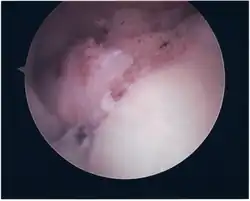

Surgical treatment of SLAP tears has become more common in recent years. The success rate for repairing isolated SLAP tears is reported between 74-94%.[10] While surgery can be performed as a traditional open procedure, an arthroscopic technique[11] is currently favored being less intrusive with low chance of iatrogenic infection.[12]